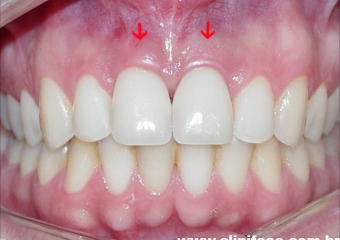

Sorriso final do caso terminado em julho de 2005

Controle do caso, realizada em janeiro de 2012.